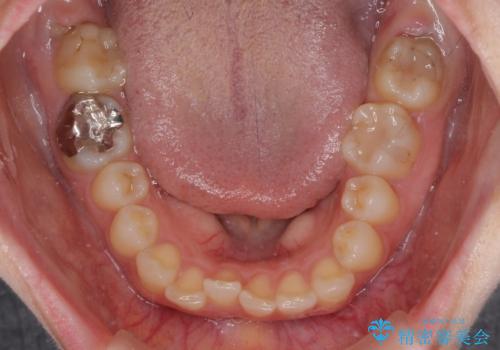

上下ともにデコボコの程度は著しいものではなく、インビザラインで十分に対応可能な歯列不正でした。

後戻りによりスペースができてしまうことを避ける目的で、IPR(歯と歯の間を削る)を極力用いない矯正治療を行うこととしました。